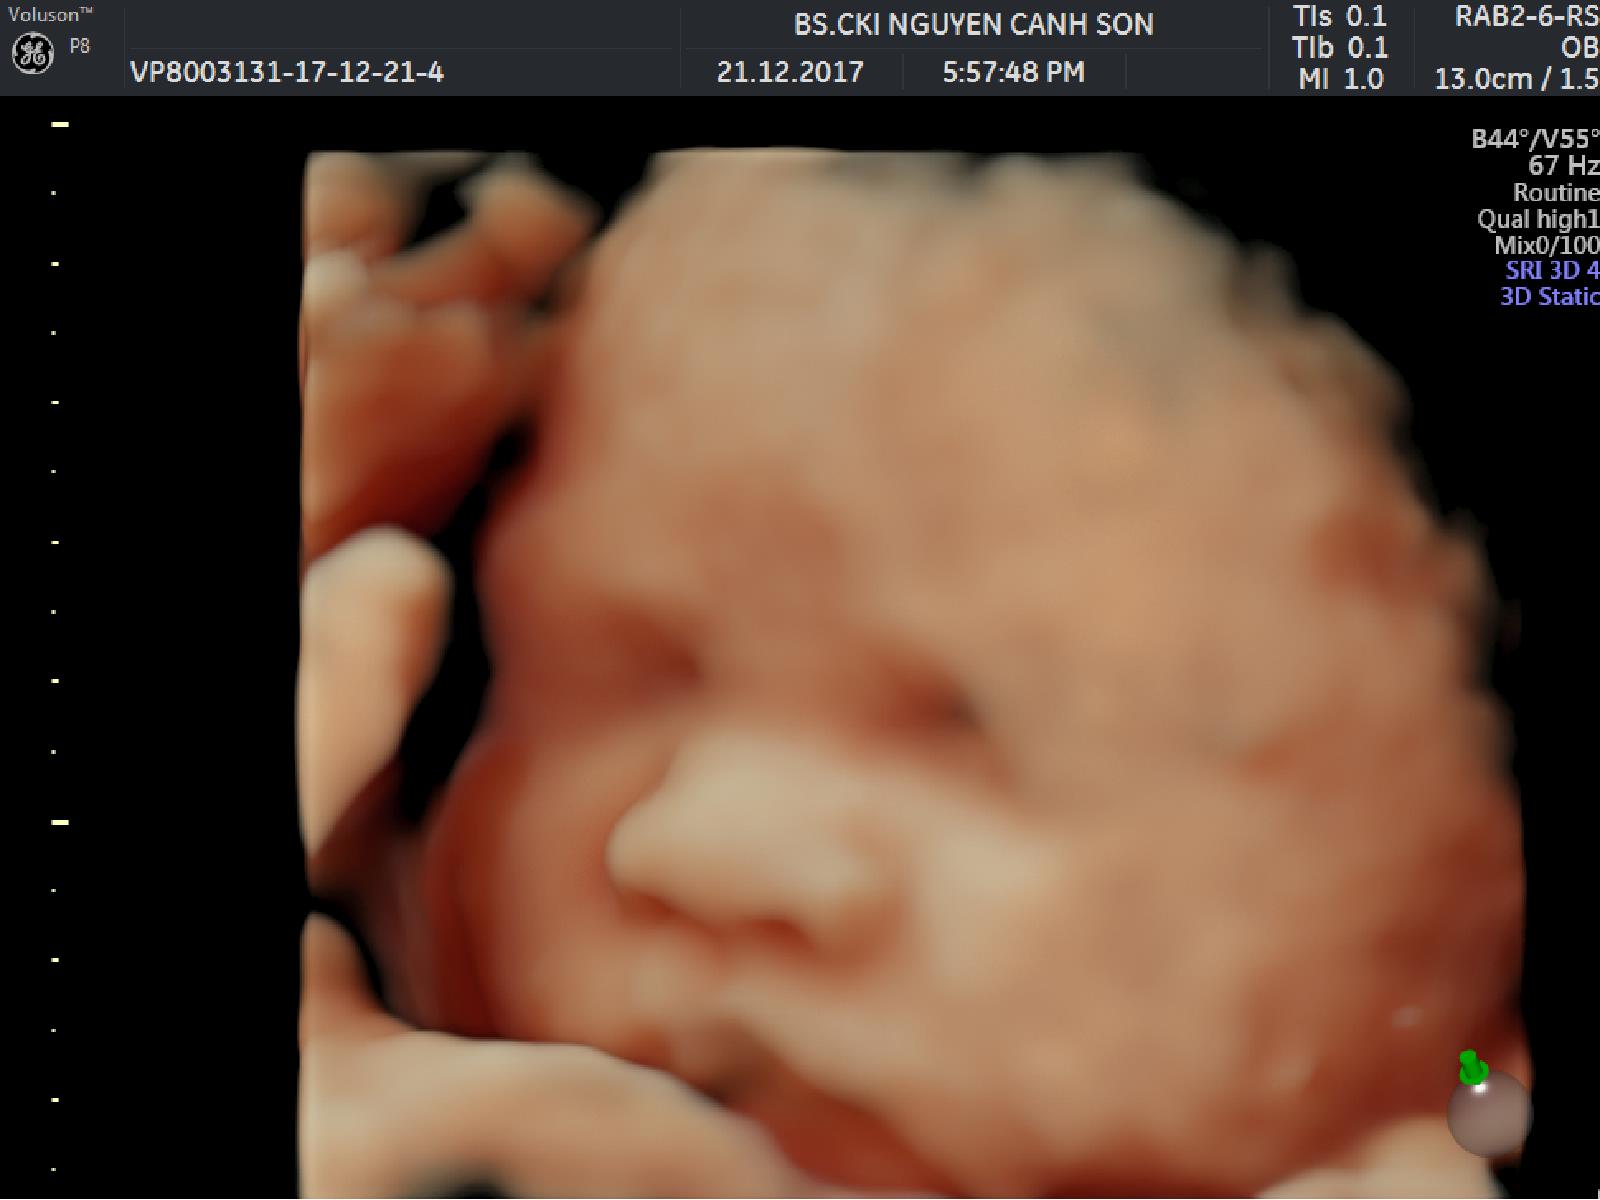

Siêu âm